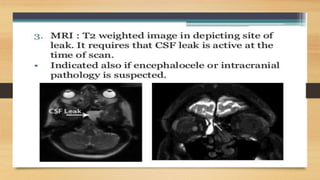

• 14.

Imaging : 1. HighResolution CT Scan:  Initial imaging study of choice.  Should have 1mm cuts with axial, sagittal and coronal views.  Sensitivity and specificity > 90%.